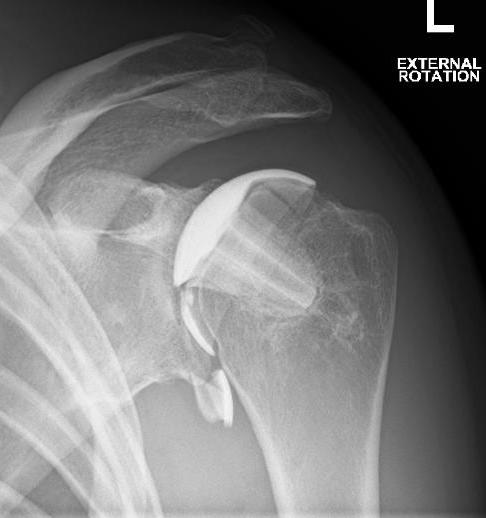

TSR Anterior Instability LateralTSR Anterior Instability AP

Posterior

Cause

- excess retroversion of glenoid or humerus

- posterior glenoid erosion

- soft tissue imbalance

TSR Posterior DislocationRevision for Posterior Dislocation TSR Combined Anterior Posterior Approach